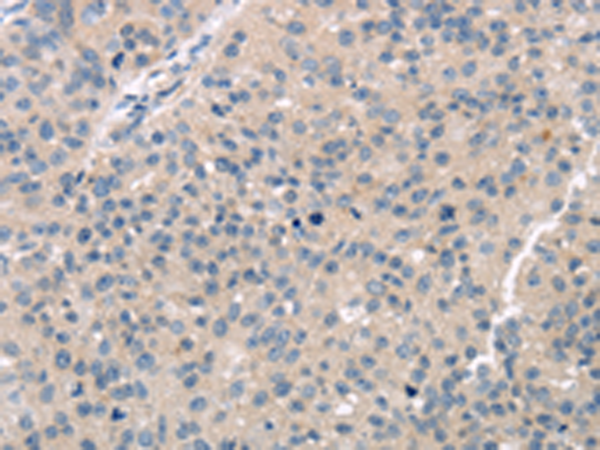

分类: 科研抗体货号: P08917别名: HCC-8应用: WB,IHC反应种属: Human, Mouse